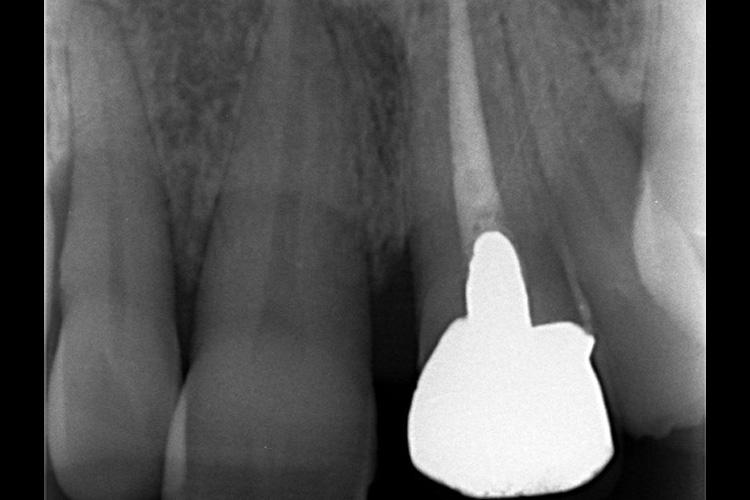

この患者様は、口腔内全体において重度の歯周病が生じており、歯磨き指導、クリーニング、Flap手術等を行ったが、歯周ポケットが深すぎるためブルーラジカル適用症例と診断し、施術を行いました。

施術前のレントゲンと口腔内写真です。施術前にプラークの除去を行ってから、施術します。